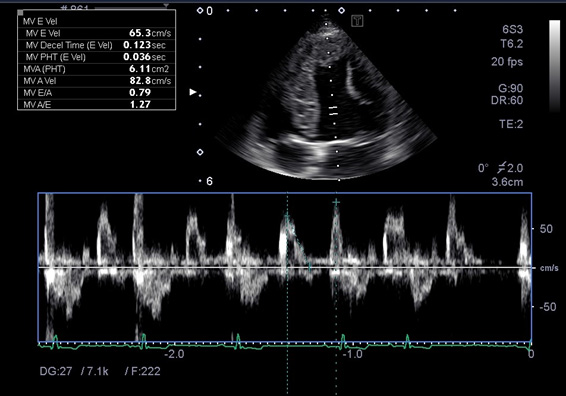

僧帽弁閉鎖不全症